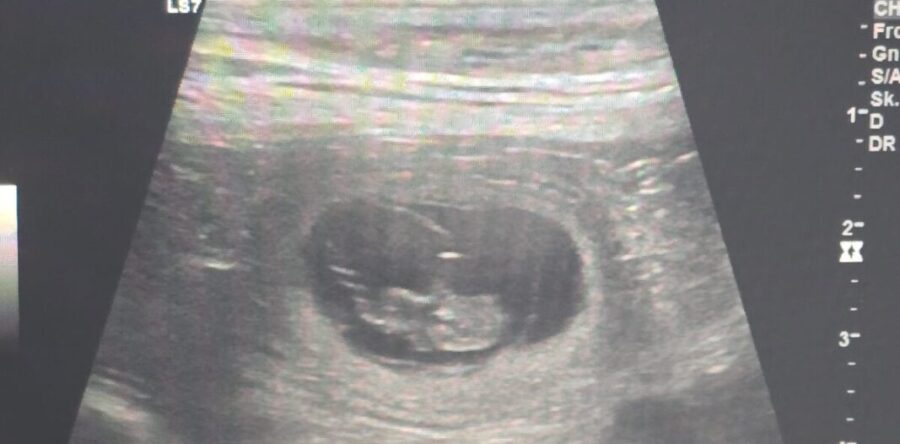

Heute ist der Tag der Tage, hat es geklappt oder nicht??? Jaaaaa, es hat geklappt. Wir sind glücklich, dass das was uns Branka eigentlich schon gezeigt hat, jetzt offiziell ist. Sie ist Tragend. Die Tierärztin hat auf einer Seite am Bauch geschallt und hat auf Anhieb 3 Föten gesehen. Sogar den Herzschlag konnte man erkennen.